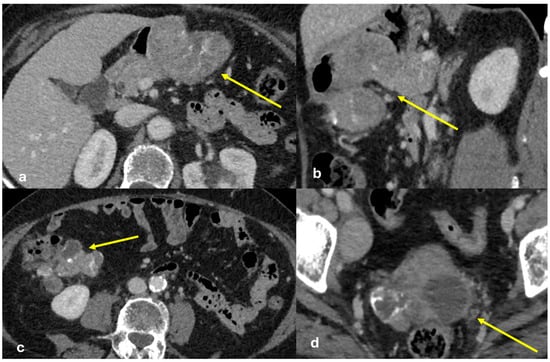

3.3.4. Subperitoneal Spread of Necrotizing Pancreatitis

3.3.6. Peritoneal Tuberculosis